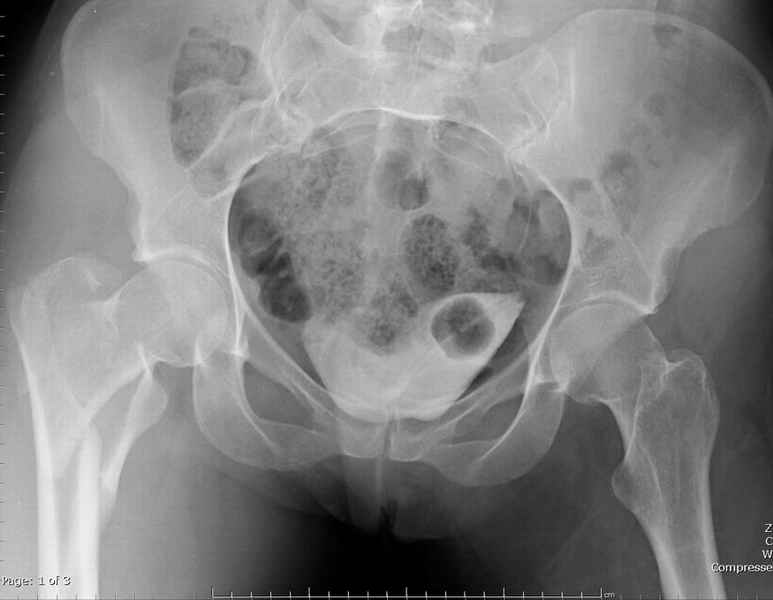

Ap pelvis Rt sub-intra trochanteric Fracture

Ap pelvis Rt sub-intra trochanteric Fracture, AP Rt hip, Postop Blade Fixation